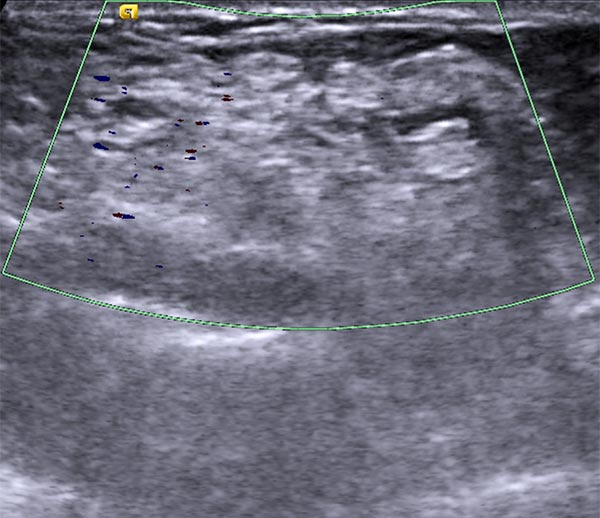

Die Duplexsonographie nach multiplen Sklerosierungen zeigt einen fast vollständigen Verschluss der dysplastischen Venen. Keine Farbsignale mehr in der jetzt echoreichen Läsion, die keine offenen, dysplastischen Venenkanäle mehr zeigt.